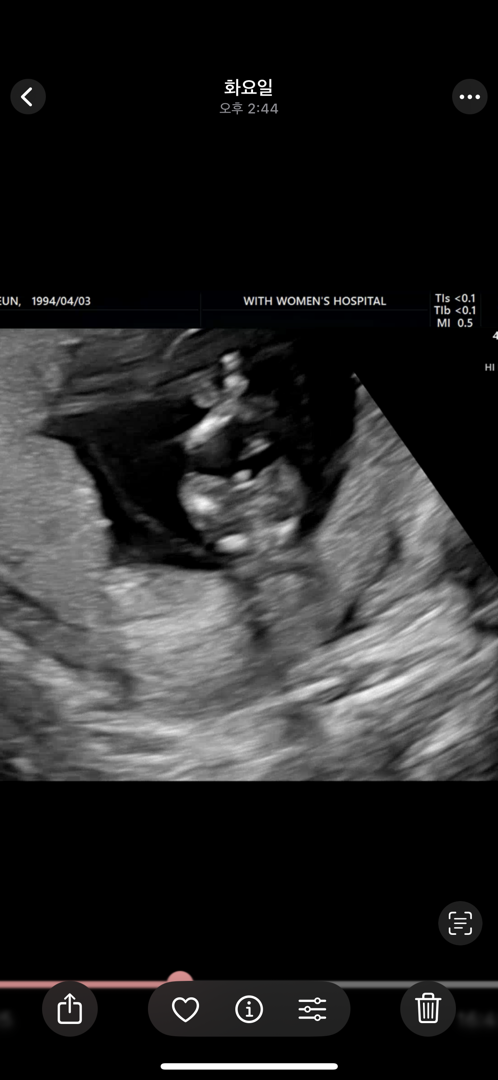

12주 다리사이 한번 봐주세요!!

다리사이에 탯줄 감고 있다고 하시긴한데 탯줄같나요 고추같나용 ㅠㅠ?

고추같아요 ㅎㅎ

아들같아용